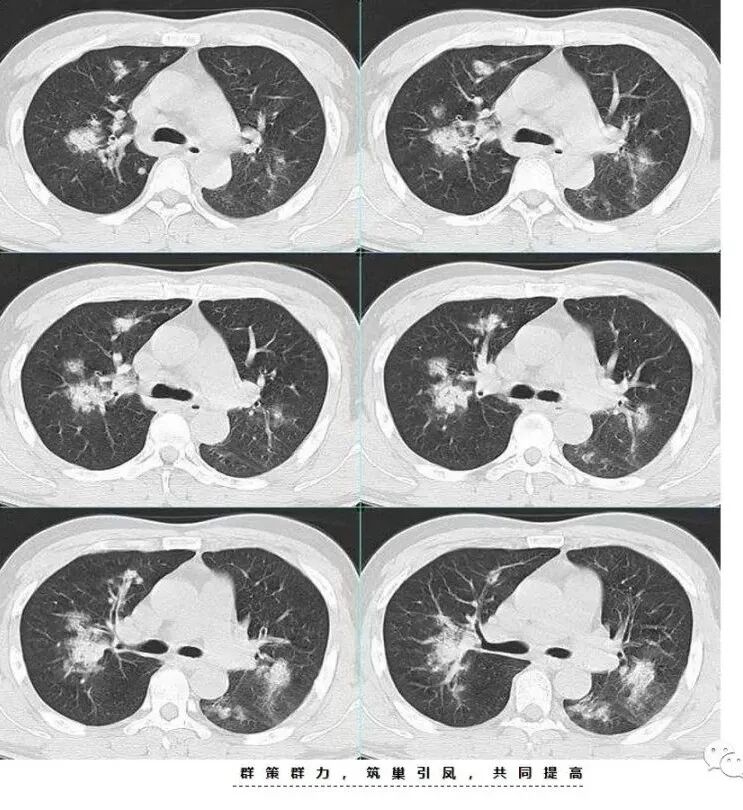

中年男性,咳嗽咳痰伴咯血胸疼,发热。双肺野多发斑片磨玻璃影实变影,结节影,结节影大小不一,主要沿支气管血管束分布,边界清楚,支气管进入,有支气管充气征,左下肺大片实变影,周围磨玻璃影,边界不清,考虑粘液腺癌并双肺转移,鉴别淋巴瘤,血管炎,机化性肺炎。

老年男性,急性起病,伴发热、咳血,双肺多发结节、片状高密度影及磨玻璃密度影,边缘模糊不清,支气管穿行,考虑感染性病变,金葡菌,建议抗炎治疗后复查除外粘液腺癌

中年男性,咳嗽发热伴咳血胸痛。以左下肺大片实变混合磨玻璃为主,另两肺散在斑片状阴影,渗出明显边缘模糊,左下肺病灶部分边缘平直,病灶内未见明显空洞气囊等,未见树芽。纵隔窗显示病灶范围明显缩小提示渗出为主,双侧胸腔未见明显积液。首诊还是感染性病变,细菌,真菌,病毒,气道播散型金葡菌?非典型肺炎?

两肺多发磨玻璃结节、斑片及实变,沿支气管血管束分布,部分边界清,左肺下叶大片实变,考虑腺癌,鉴别血管炎

男,52,咳嗽咳痰胸痛半月,近期加重,发热3天,声嘶伴气短1天,昨晚痰血。胸部CT:双肺多发斑片影、结节影,大小不一,密度不一,有GGO、有实性,沿支气管血管束分布,中内带多,边界不清,支气管进入,支气管充气征,似有小叶内间隔增厚,考虑:血管炎?肺水肿?鉴别感染、腺Ca、淋巴瘤等。